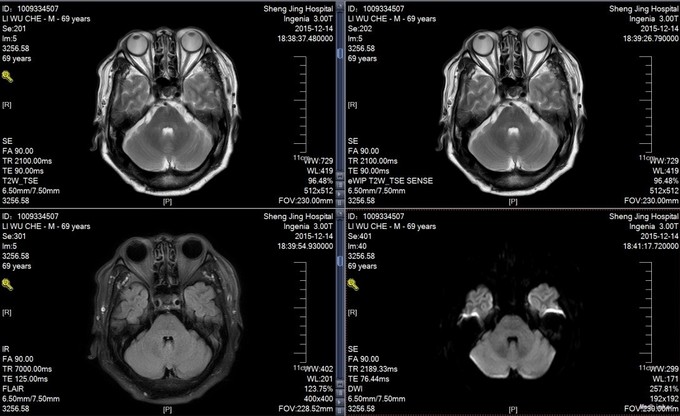

1.患者老年男性,69岁,急性起病,以“头晕3天,加重1天”为主诉入院。 2.患者3天前无明显诱因突然出现头晕,偶有恶心未吐,无视物旋转及视物模糊,无耳鸣及听力下降,无肢体活动障碍。测量血压可达180/100mmHg,休息并服用1片开博通后可缓解。昨日晚10点头迷突然加重,伴视物旋转,无恶心呕吐,不敢睁眼及活动,测量血压180/100mmHg,休息后并口服1片开博通未见缓解。遂拨打120来我院急诊科,测量血压达200/110mmHg。给予对症治疗后头晕略见好转,现为求进一步诊治来我科住院。患者病来无意识障碍,无抽搐,无饮水呛咳及吞咽困难,无四肢活动障碍。无胸痛及气短,无腹痛腹泻。饮食可,睡眠尚可,二便正常。近期无明显体重变化。 3.既往史:高血压病史十余年,最高达200/120mmHg,平时硝苯地平控释片及厄贝沙坦片口服控制血压,血压稳定在150/90mmHg左右;否认冠心病、糖尿病病史;于今年6月份因头晕恶心呕吐在医大一院就诊,诊断多发腔梗,病情好转后出院;于今年10月份因头晕恶心呕吐来我科就诊,诊断椎基底动脉供血不足,病情好转后出院;否认手术外伤史,否认输血史,否认肝炎、结核等传染病史。 过敏史:否认药物及食物过敏史。 个人史:否认吸烟及饮酒史。 家族史:否认家族遗传病史。

椎基底动脉供血不足 给予营养神经,改善循环,抗血小板,抗动脉硬化,抗氧化治疗,介入科会诊意见,该患者不适合手术治疗。

椎基底动脉供血不足是临床上常见疾病,但对于该患者,基地动脉狭窄明显,多次因头晕住院治疗,内科保守治疗效果有限,必定发展为急性脑梗塞,但介入对于后循环治疗尤其是基底动脉治疗风险非常大,对于患者的治疗有种束手无策的感觉,希望将来能够有更好的治疗办法。